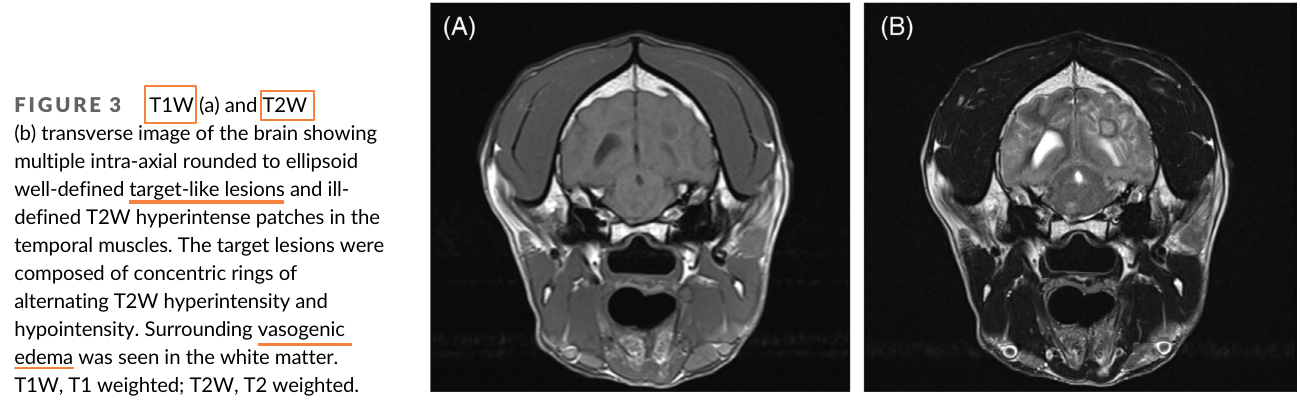

칸디다는 곰팡이성 질환으로 보통 거론되는 게 에이즈 환자등, 면역계가 무너진 환자에서 이차적 기회감염에 해당하는 부분이다. 개에서도 마찬가지로 대부분 면역 억제 치료를 받을 때 주로 증상이 나타날 수 있는데 이번 증례는 뇌에 감염이 있을 때의 증례, 특히 MRI 촬영과 부검을 통한 재확인이 매우 가치 있는 논문이라 하겠다.